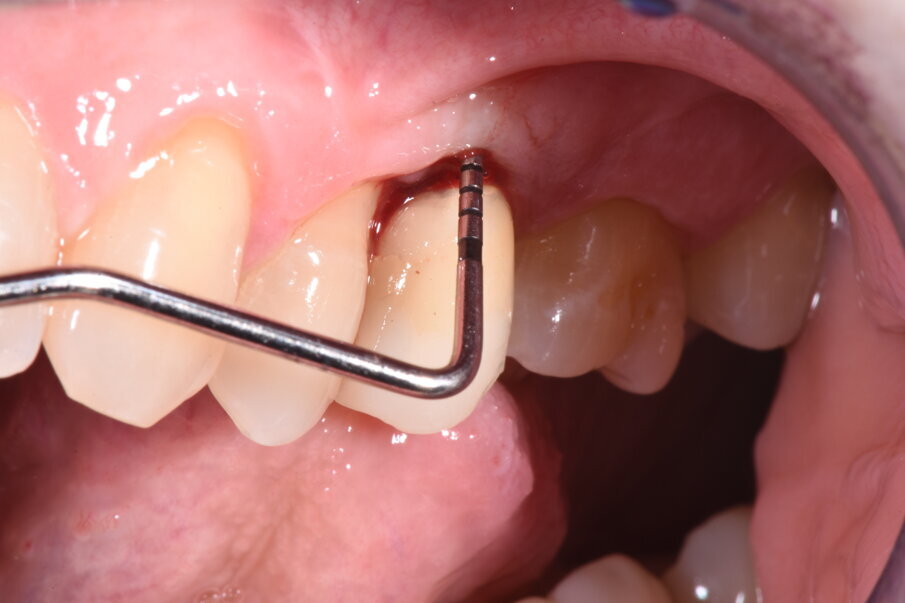

La paziente si presenta all’attenzione dello studio riferendo fastidi nella zona superiore sx, e all’anamnesi risultano trascorsi 3 anni dall’ultimo appuntamento di igiene presso altro centro. L’esame visivo e fotografico (Fig. 1) evidenziano un’alterazione dello stato dei tessuti perimplantari con sanguinamento spontaneo e lassità del tessuto molle, pertanto segue acquisizione di rx endorale da parte dell’odontoiatra (Fig. 2) da cui risulta un’importante riassorbimento osseo a carico dell’impianto. Segue un sondaggio perimplantare profondo (Fig 3), eseguito previa anestesia topica con Lidocaina 15%, per definire estensione e conformazione del difetto associandolo alla valutazione radiografica per la conta delle spire esposte.

Fig. 1

Fig. 3

Si definisce un difetto con tipico aspetto a scodella, esteso a tutta l’area del perimpianto. Dalla sovrapposizione tra sondaggio ed esame radiografico, si evidenzia perdita del picco osseo distale all’elemento 14 indicando una prognosi peggiore dell’elemento implantare.